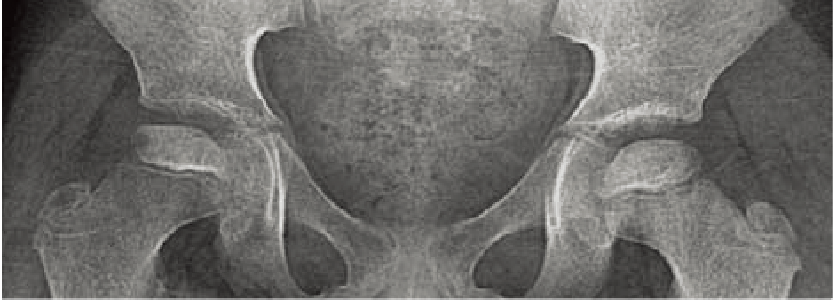

特徴的な画像所見:腸骨稜の不規則なレース様所見(lace-like appearance)が特徴的である(A)。脊椎は中等度の扁平椎を呈し、側面像ではひょうたん状の椎体変形(double hump)を認める(B)。長管骨では骨端異形成が著明で、特に大腿骨頭の骨化は遅延する。

A. 両股関節正面像(8歳、男):腸骨稜のレース様所見と大腿骨頚部の短縮を認める。